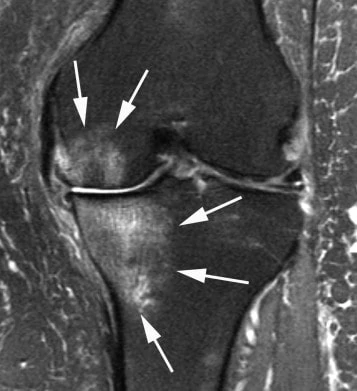

Najčešći simptom uznapredovale gonartroze je bol u kolenu, često sa unutrašnje ili spoljne strane, napred, pozadi ili čak niz potkolenicu. Bol može biti praćen ograničenim pokretima, šepanjem, otokom i osećajem nestabilnosti.

- Dijagnoza se postavlja pregledom ortopeda i snimcima.

- Rendgen pod opterećenjem je veoma važan za procenu suženja zglobnog prostora, osovine kolena, osteofita i stepena propadanja.

- Po potrebi se rade dodatne analize i dopunska snimanja.